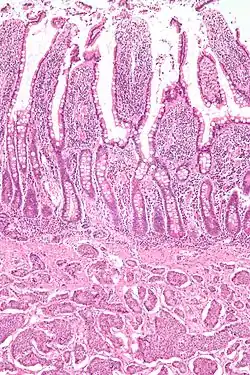

NETs are often small, yellow or tan masses, often located in the submucosa or more deeply intramurally, and they can be very firm due to an accompanying intense desmoplastic reaction. The overlying mucosa may be either intact or ulcerated. Some GEP-NETs invade deeply to involve the mesentery.[72] Histologically, NETs are an example of "small blue cell tumors," showing uniform cells which have a round to oval stippled nucleus and scant, pink granular cytoplasm. The cells may align variously in islands, glands or sheets. High power examination shows bland cytopathology. Electron microscopy can identify secretory granules. There is usually minimal pleomorphism but less commonly there can be anaplasia, mitotic activity, and necrosis.